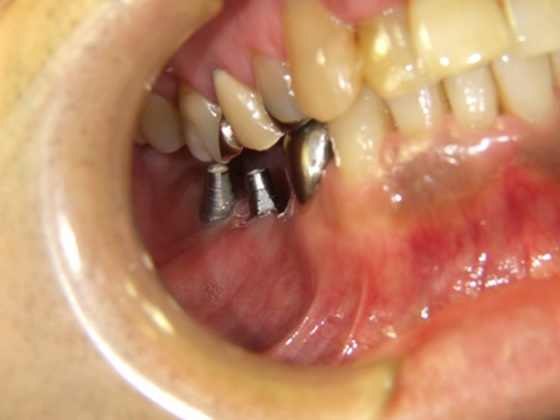

50歳代 男性 右下臼歯部 インプラント植立

セラミック冠を装着したところ(横から)